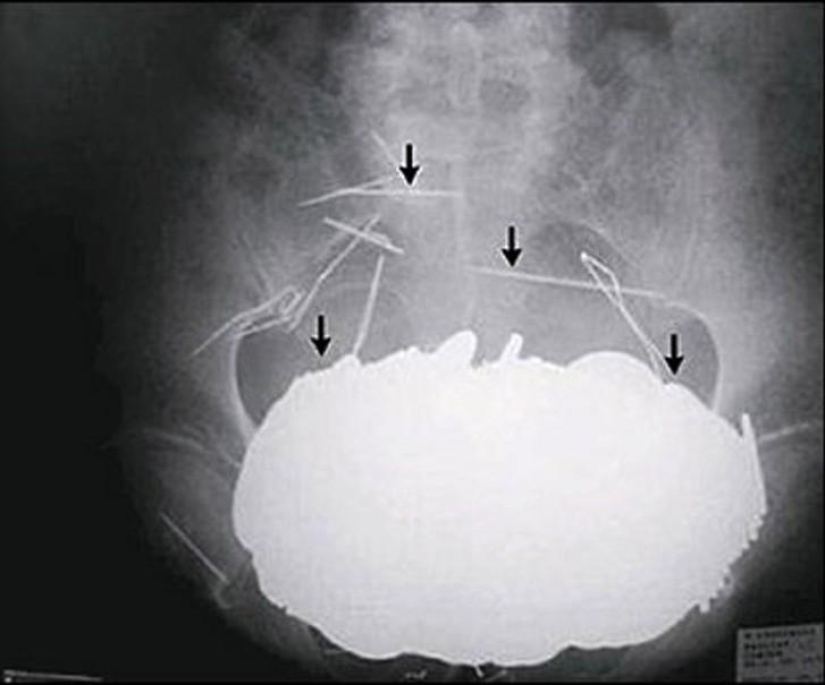

12. Cubiertos.